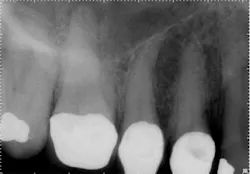

For example, in canal anatomy that appears to be fairly straight on preoperative radiographs in roots with traditional taper, a single file system such as WaveOne(Dentsply Tulsa Dental Specialties) would be an excellent choice to achieve cleanliness and shape (Figs. 1 and 2). The single-file reciprocating system would also have the added benefits of simplicity and efficiency.

In these three cases, different instrumentation systems were used to create the final shape of the root canal system. In spite of differences in the number of files used, the file design and file movement, the end results look very similar. Although potentially confusing to clinicians, the advances in metallurgy and file design allow for safer and more efficient cleaning and shaping of the root canal system than ever before. However, despite these advances, the success rates of endodontic treatment have stagnated over the last several decades, indicating there is more to clinical success than a dense, white line on a radiograph. Canal shaping is important, but it is paramount that an effective irrigation protocol is incorporated into the endodontic procedure to safely and effectively eliminate all possible bacteria.Fig. 1: Although access is usually an issue when treating second molars, the shape of the roots and good chamber size suggest WaveOne would be an ideal file system for tooth No. 2.

Fig. 2: Following establishment of a glide path and removing the dentin triangle, a single WaveOne primary file was used to create the final shape. This shape would allow for deep and safe delivery of irrigants and maximum disruption of biofilm.